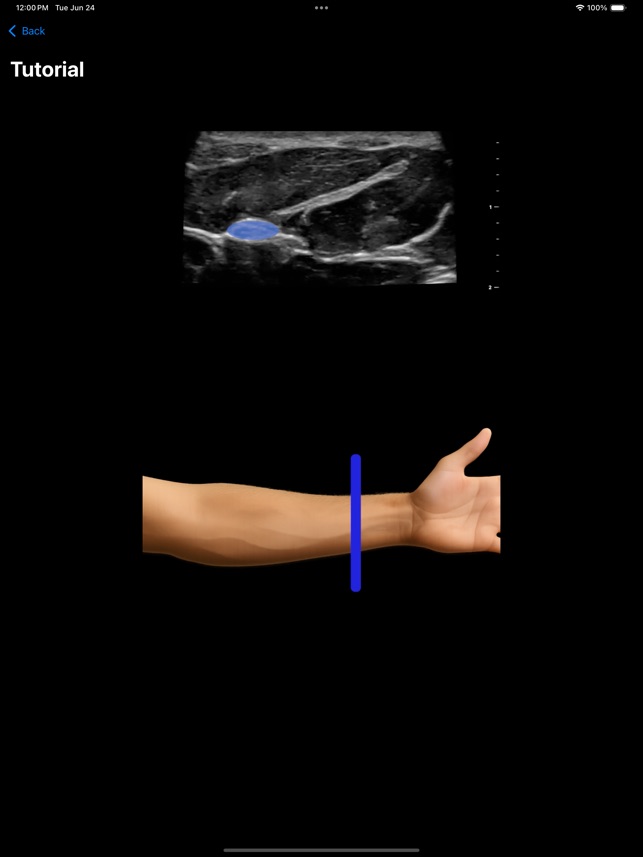

MSK VUE is a specialized training application for musculoskeletal ultrasound. The system utilizes an artificial intelligence component to support the identification of key peripheral anatomical structures within an interactive, simulated ultrasound imaging environment. The interface is designed to present visualizations of nerves, tendons, and bones, allowing users to engage with the simulated data. This application's core mechanism focuses on presenting specific anatomical targets and facilitating their recognition through its AI-driven framework, providing a platform for practice in a non-clinical context.

This application is designed for clinicians seeking to develop proficiency in musculoskeletal ultrasound. It functions as a supplementary educational tool for practicing the identification of peripheral anatomical structures within a simulated environment. This app is intended for educational purposes and does not replace professional medical advice, diagnosis, or treatment; the provided description explicitly prohibits its use in any clinical setting or for any clinical purposes.